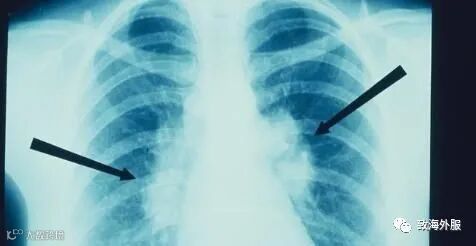

肺纹理是啥:胸部x片上提示的肺纹理其实就是气管、动脉、静脉,共同汇合在一起形成的影子。因为他们是紧密相邻,有时又有重叠,在胸片上根本就没有办法区分哪一个是气管,哪一个是动脉,哪一个是静脉,所以把他们重叠的影子统称为肺纹理。

肺纹理如何分布:可想而知,由于靠近中间的气管、动脉、静脉都相对比较粗大,所以正常情况下,胸部x片靠近中间的部分会纹理比较明显,越靠外边缘越不明显,到了外1/3,肺纹理就很细小了,因为那里只有一些毛细血管和肺泡,就像拿着一根细线来拍照,看不出什么东西来。